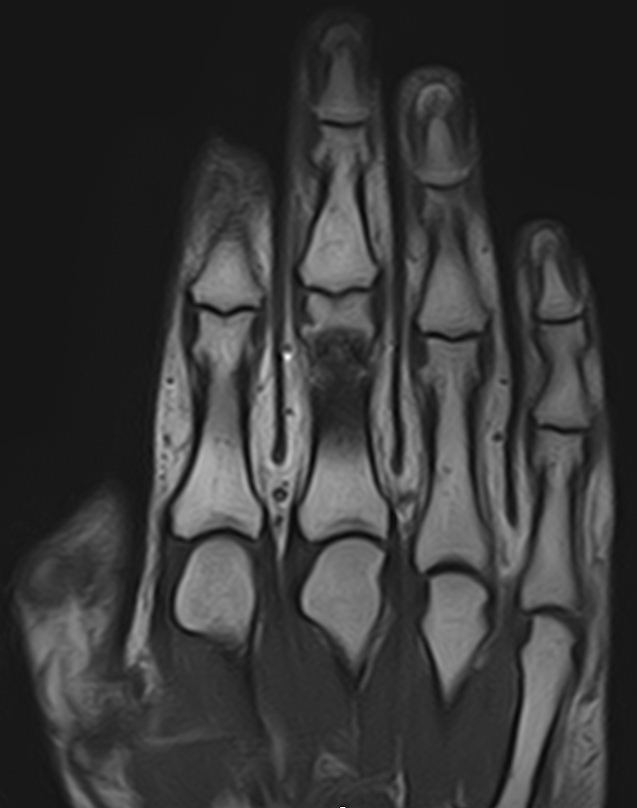

Современным и высокоточным методом диагностики заболеваний кистей рук является магнитно-резонансная томография. МРТ дает наиболее полную информацию о состоянии костей, суставов, связок, сухожилий, нервных волокон и мягких тканей кисти. Дополнительным преимуществом МРТ является ее безопасность, так как в основе метода лежит использование внешнего магнитного поля без применения ионизирующего излучения. При необходимости это позволяет выполнять исследование неоднократно в течение короткого периода времени.

Клиника «Доступная медицина» располагает новейшим 32-канальным высокопольным томографом закрытого типа TOSHIBA VANTAGE TITAN 1,5 Тесла, который позволяет получать изображения зоны кистей рук с высокой степенью детализации. Данные, полученные по результатам МР томографии, дают возможность врачу поставить точный достоверный диагноз и назначить своевременное лечение.

МРТ кисти руки – это высокоспецифичный метод визуализации мышц, связок, хрящей, костного мозга, жировой ткани.

С его помощью обнаруживаются:

• деструктивные изменения в суставах;

• утолщение синовиальных оболочек, выстилающих суставные полости;

• воспалительные выпоты ;

• краевые дефекты костной ткани;

• растяжения, разрывы связок , сухожилий сгибателей — разгибателей;

• субхондральные кисты (деградация кости вокруг суставного хряща);

• доброкачественные новообразования мягких тканей пальцев кисти (нодулярный теносиневит, сухожильный ганглий);

• злокачественные опухоли (остеосаркомы, мягкотканные саркомы ).

МРТ сухожилий и мягких тканей кисти руки помогает с постановкой окончательного диагноза, установленного при помощи других методик.